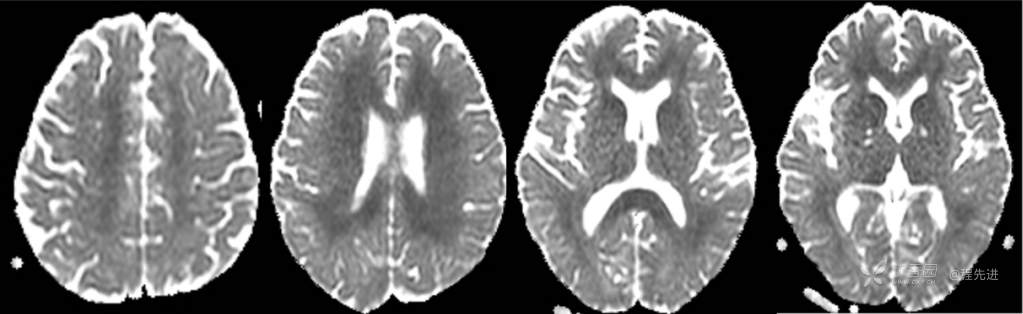

CT平扫

T2

FLAIR

DWI

ADC